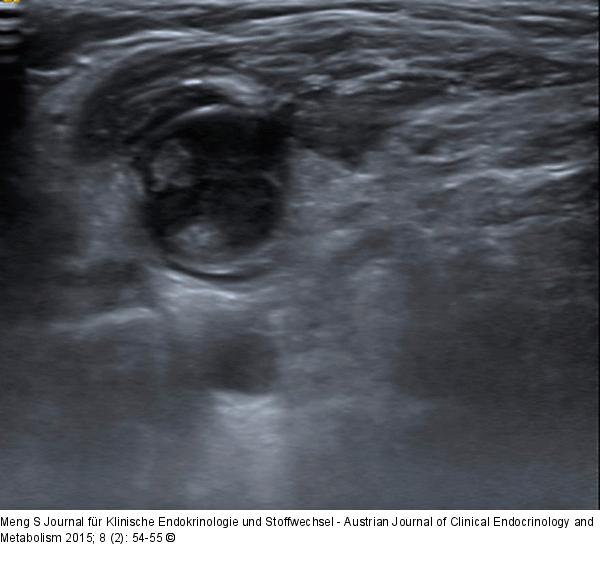

Abbildung 9: Ultraschall-Lymphknoten Begrenzung. Bei diesem Lymphknoten fällt eine Unterbrechung der scharfen Begrenzung auf 11 Uhr auf. Hier infiltriert ein fingerförmiger Tumorausläufer aus dem Lymphknoten den Musculus sternocleidomastoideus. Tonsillenkarzinommetastase. |